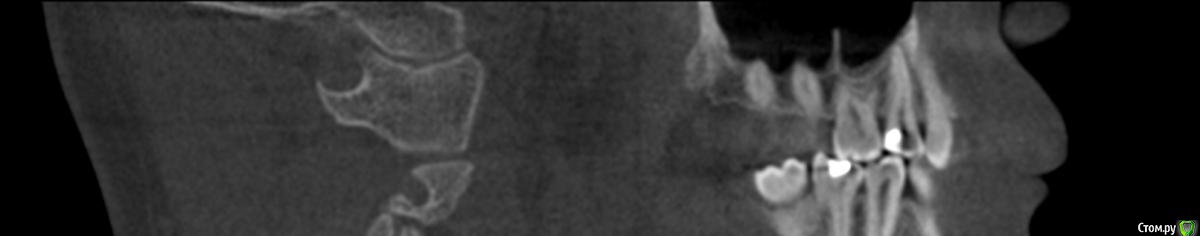

kozloff Опубликовано 15 ноября, 2015 Поделиться Опубликовано 15 ноября, 2015 Да, нужно исключить синусит.А еще можно заподозрить дисфункцию ВНЧС, на вашем снимке (ОПТГ) вызвает опасение расположение суставных головок. Но это может быть дефект снимка.Обязательно сделайте КТ, на одном снимке можно и пазухи рассмотреть, и ВНЧС. Ссылка на комментарий

kozloff Опубликовано 18 ноября, 2015 Поделиться Опубликовано 18 ноября, 2015 Подозреваю пульпит зуба 25И к лору не помешает сходить, есть отек слизистой. Гайморита нет. Ссылка на комментарий

Jurai Опубликовано 22 ноября, 2015 Поделиться Опубликовано 22 ноября, 2015 Есть проблема во фронтальном участке верхней челюсти: общая убыль костной ткани, ячеистая структура кости. смещение зубов так, что корни изогнулись, это значит, что либо резорбция (рассасывание) либо очень длительное уже идет воздействие. Могу подозревать новооборазование в этом участке.Вам нужна консультация челюстно-лицевого хирурга-онколога. 1 Ссылка на комментарий